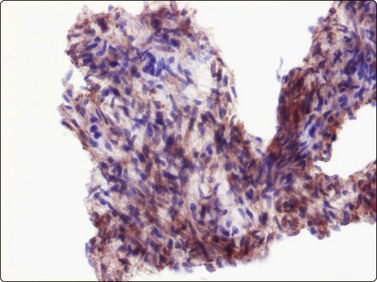

Other benign fibroblastic/myofibroblastic and fibrohistiocytic tumors are solitary fibrous tumor (SFT) and hemangiopericytoma. According to recent investigations of these tumors, they are considered to be closely related, most probably representing two variants of the same entity.10 SFT most commonly occurrs in the pleura. SFT of the soft tissues is most often seen in adults as a deep-seated mass. In tissue sections the tumors are variably cellular and collagenous bands and hyalinisation are common findings. The fibroblastic spindle cells have no specific features and there is generally insignificant cellular atypia. A hemangiopericytoma-like vascular pattern is often present. The cytomorphology of SFT has been described in a few cases.19,20 Bland spindle cells arranged in tight cell clusters associated with ropy collagen, as well as dispersed cells often with stripped nuclei, seem to be the typical appearance in FNB smears (Fig. 15.9A). The tumor cells stain positively for CD34 (Fig. 15.9B) and occasionally for CD99 and bcl-2.

image image

Fig. 15.9 Solitary fibrous tumour

(A) Bland, plump spindle fibroblastic cells arranged in tight cell clusters as well as dispersed cells associated with strands of collagenous stroma (H&E, IP); (B) Spindle cells staining positively for CD34 (cell block, immunoperoxidase, LP).